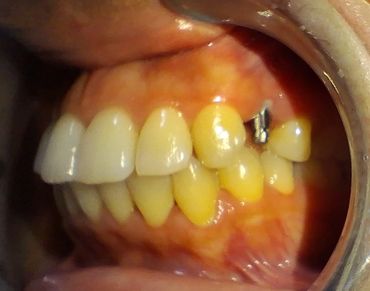

Remplacer ses dents n'est pas seulement un acte esthétique. Une dent manquante, c'est aussi, bien souvent, des difficultés à mastiquer, un déplacement des dents adjacentes qui ont tendance à verser, ou à se surélever. Ceci a pour conséquences un risque accru de caries et une malocclusion dentaire.

L’implant dentaire permet de remplacer une dent manquante de manière très esthétique avec un résultat très confortable car la dent est fixe et indépendante de ses voisines, comme une dent naturelle.

La perte d’une dent a toujours des conséquences, esthétiques, mais aussi fonctionnelles :

Parce qu’il sollicite l’os, l’implant résout tous les problèmes. Résistant et durable, il se substitue parfaitement à une racine naturelle dont il assume toutes les fonctions. Et la prothèse qu’il supporte, fabriquée sur mesure, s’intègre harmonieusement au reste de la dentition.